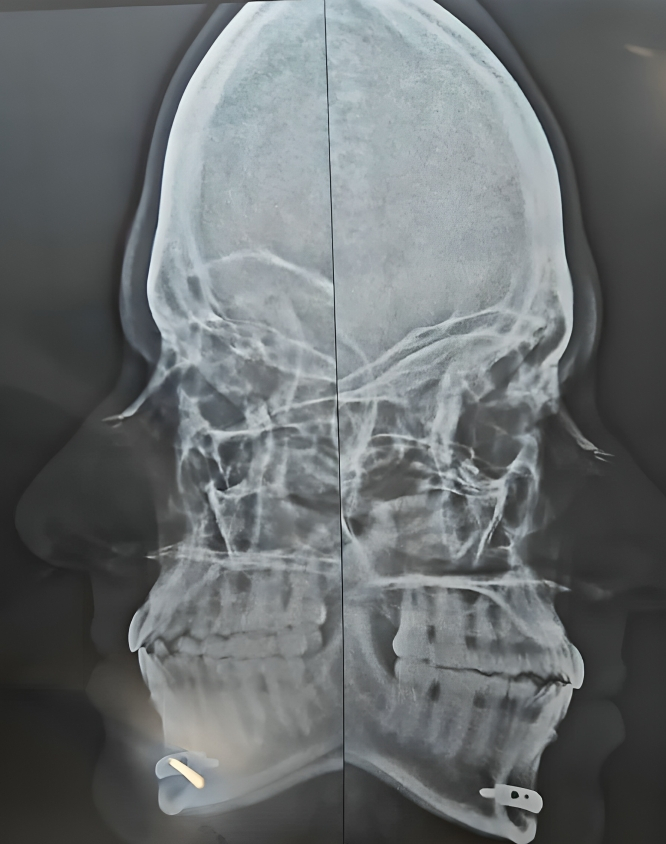

Advanced treatment for nasal blockage, sinus disease, allergies and watery eyes with Endoscopic Sinus Surgery, Septoplasty, Rhinoplasty, Dacryocystorhinostomy and Endoscopic DCR.